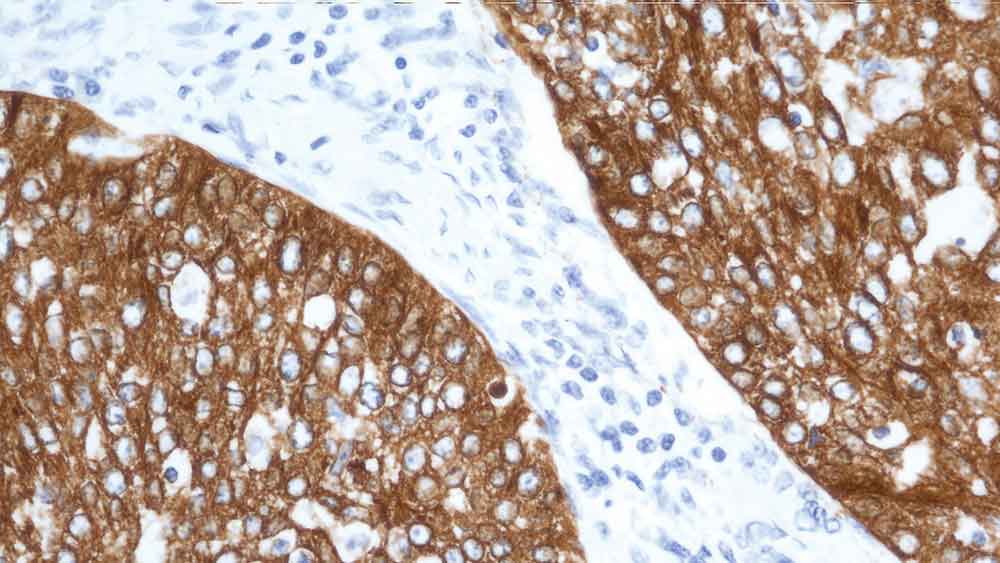

Human rectal adenocarcinoma: immunohistochemical staining for Cytokeratin 19. Note: cytoplasmic staining of malignant epithelial cells. Cytokeratin 19: clone b170

Clone B170 produces a complex heterogeneous staining pattern in non-keratinizing squamous epithelia and hair follicles, with strong staining of the basal layer observed.